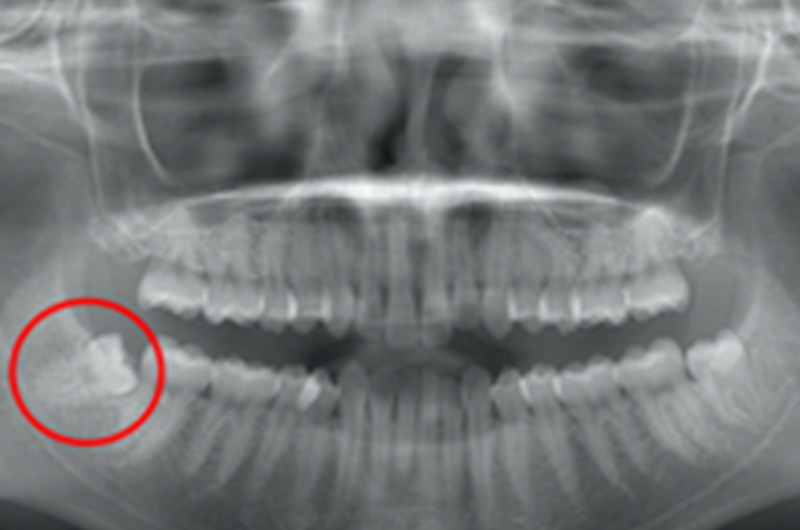

次に、今回の質問にあったような横から生えている親知らずです。親知らず周りが痛くなった時点で、智歯周囲炎になっているので、痛みが収まってから抜歯はした方が良いでしょう。痛みが収まってからのほうが良い理由は、炎症が起きていると周囲の組織が酸性になり、アルカリ性の麻酔薬は効きづらいからです。

横から生えている親知らずは、歯茎を切って、歯の引っかかっている部分を分割して、頭の部分を先に抜いてから歯根を抜いて行きます。歯根も、下一番右のレントゲン写真(CT)のように、根が3つに分かれている場合もあります。

このように、歯の根が分かれていると、骨にかみこんで引っかかってしまい、それぞれ削って分割しないと抜けません。また、真ん中のCT写真で見ると、歯の根っこも曲がっているので、こうした根が曲がっている場合も抜きにくいです。